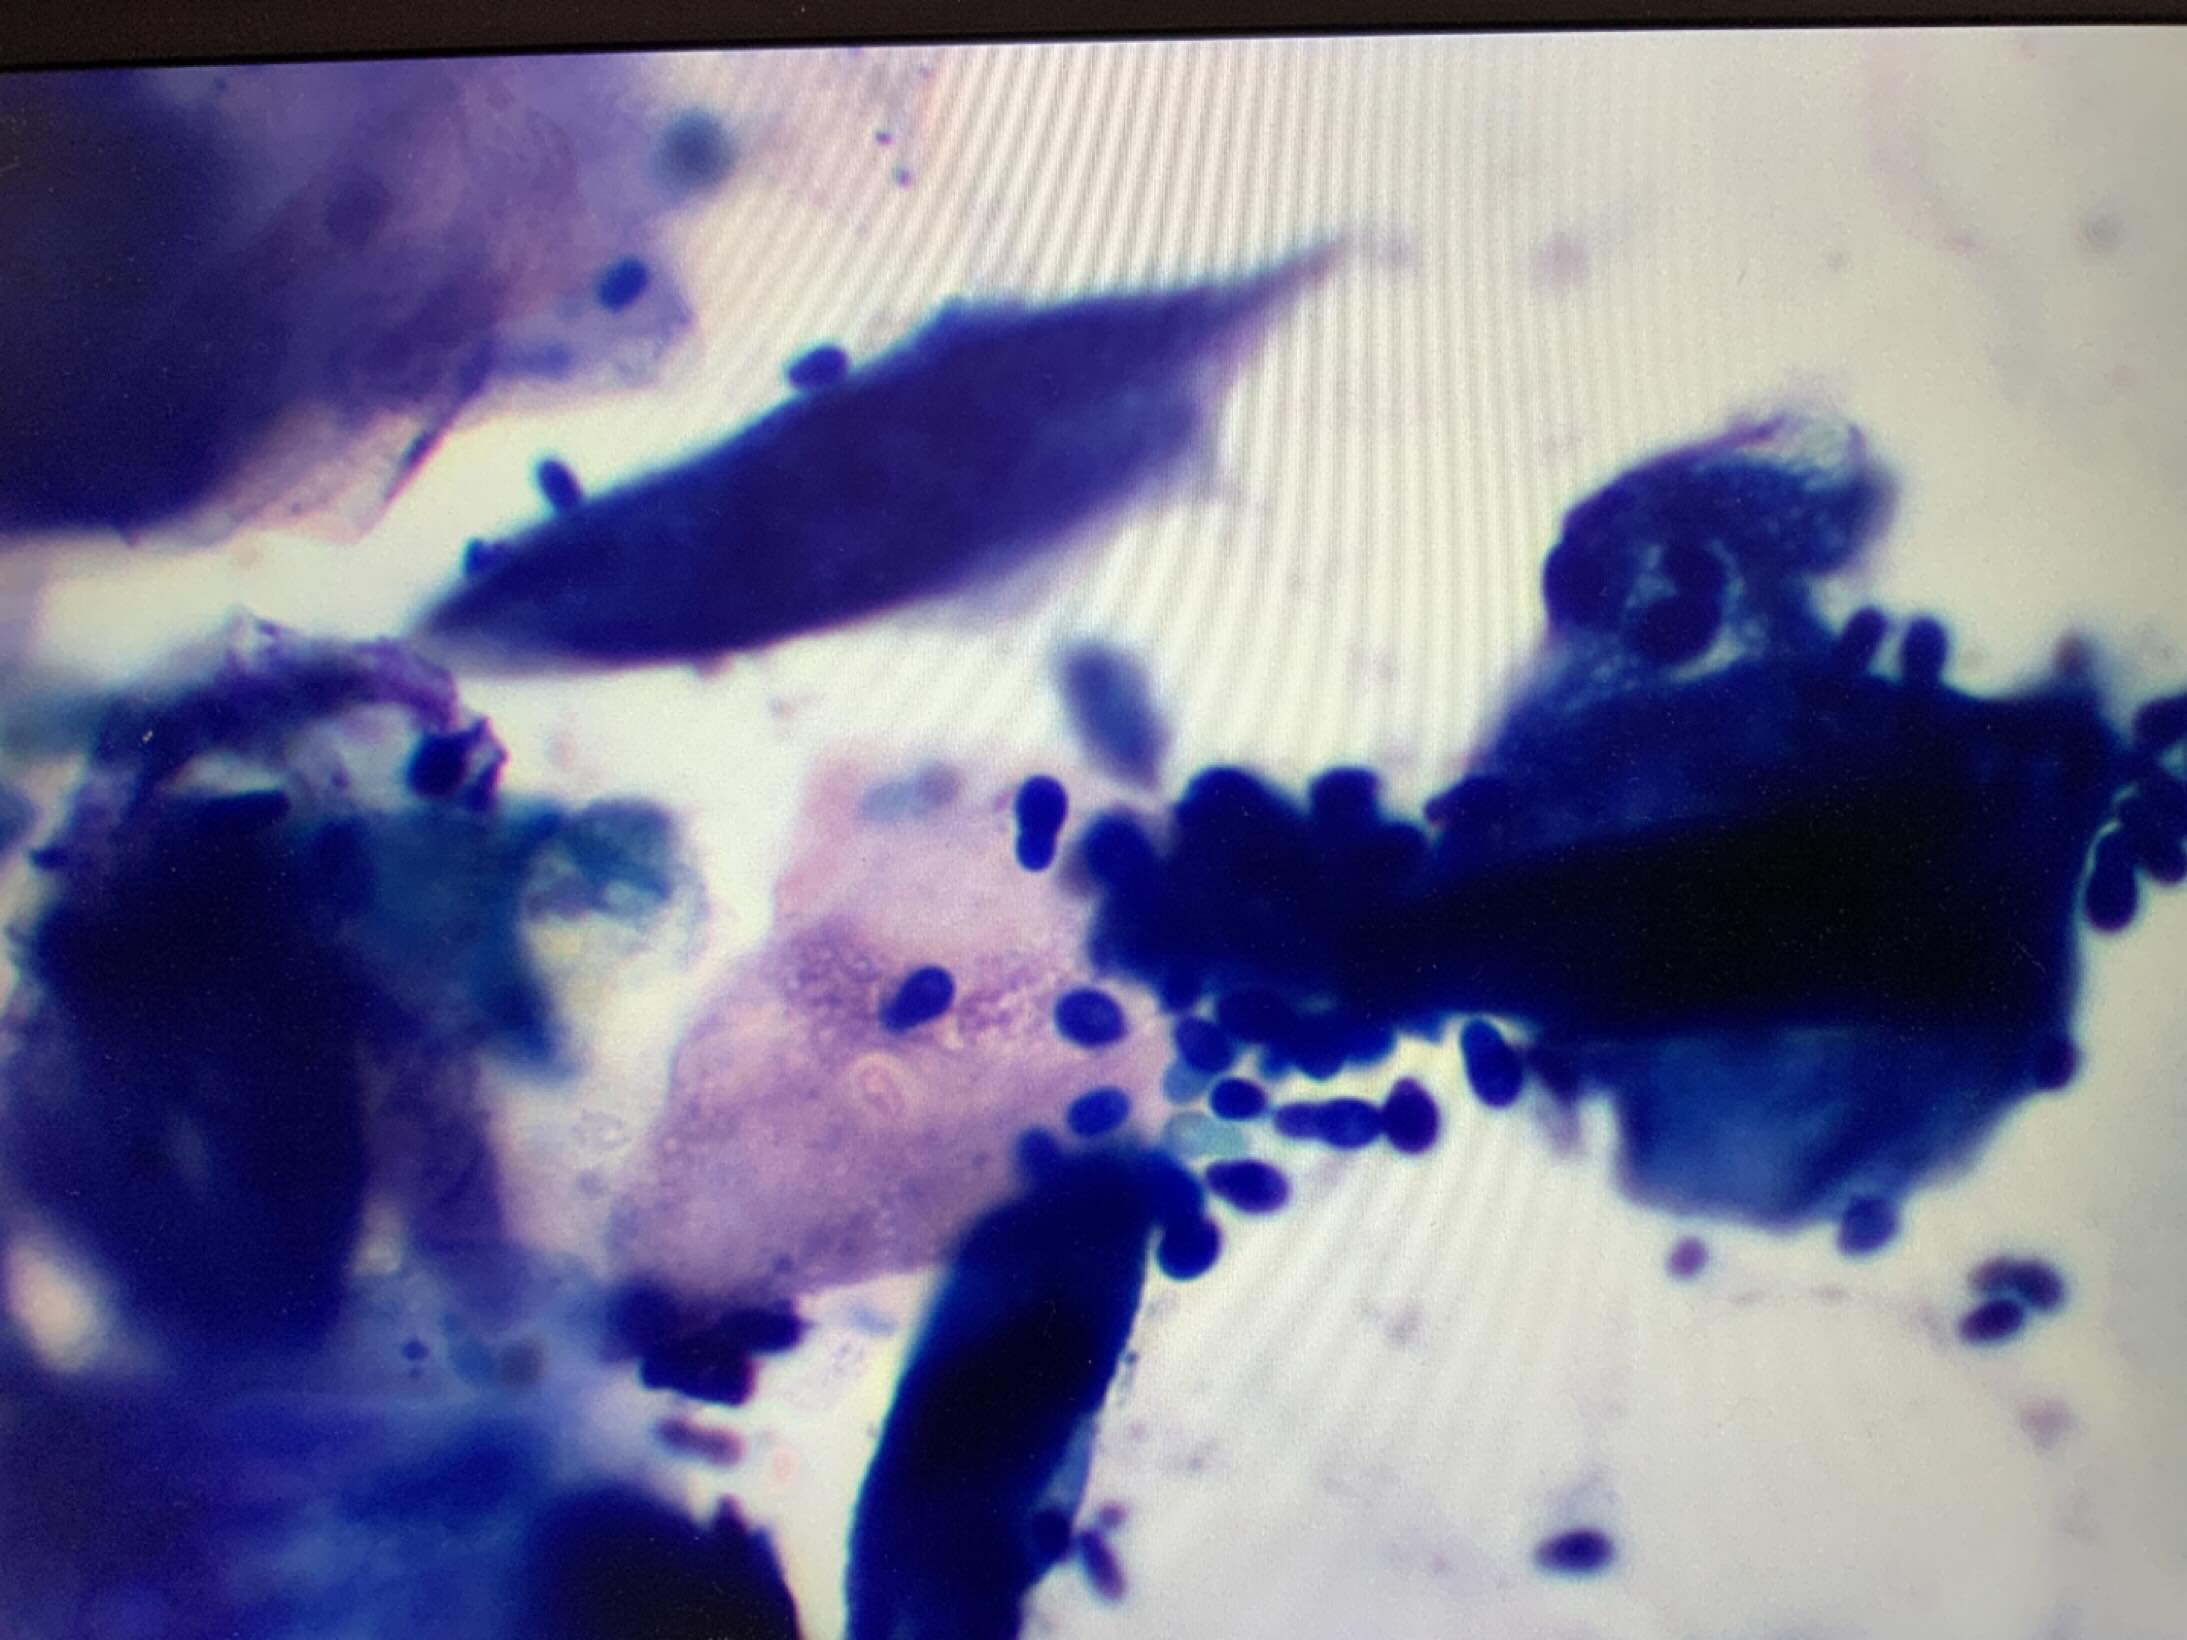

マラセチアという病原体が増殖した場合、耳の感染症の一因となり得ます。マラセチアは常在菌で「いてもおかしくない菌」なのですが,そうした菌が悪さをする場合は耳道内や体がわに原因がある場合があります。特に繰り返す場合は適切な診断と治療が必要です。